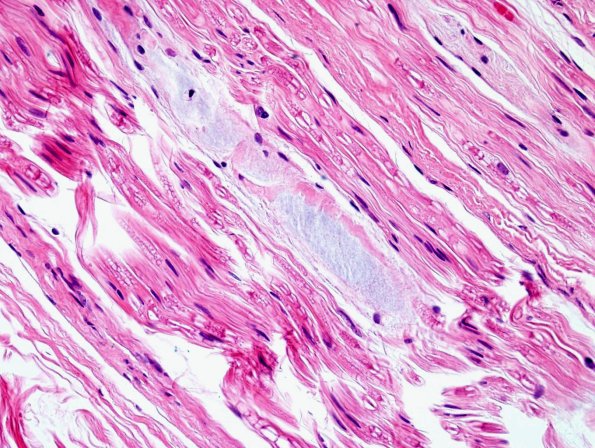

Washington University Experience | PERIPHERAL NEUROPATHY | 1 NORMAL NERVE ANATOMY | 8 Renaut bodies | 5A4 Renaut body-oma (Case 5) H&E 6

These longitudinal sections show the subperineurial extension and variation in compaction in these RB. (H&E)